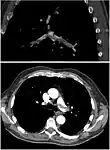

CT pulmonary angiography

CT pulmonary angiography (CTPA) is a pulmonary angiogram obtained using computed tomography (CT) with radiocontrast rather than right heart catheterization. Its advantages are that it is accurate, it is non-invasive, it is more often available, and it may identifying other lung disorders in case there is no pulmonary embolism. The accuracy and non-invasive nature of CTPA also make it advantageous for people who are pregnant.[59]

On CT scan, pulmonary emboli can be classified according to the level along the arterial tree.

Segmental and subsegmental pulmonary emboli on both sides

CT pulmonary angiography showing a "saddle embolus" at the bifurcation of the main pulmonary artery and thrombus burden in the lobar arteries on both sides.